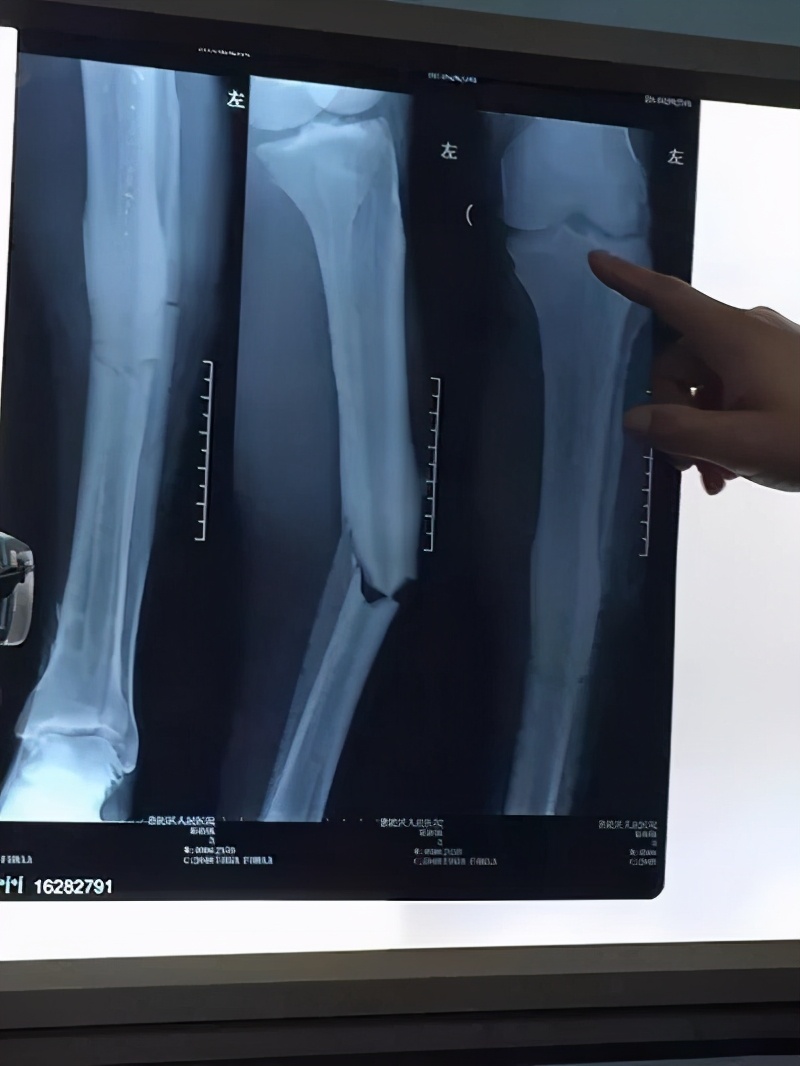

郑教授表示:“登巴巴受伤时,我们在电视画面看的很清楚,是一种横向直接*力暴**引起的,小腿中段成角畸形,胫腓骨完全断裂,从他的X光片看是胫腓骨横断骨折,也属于一种简单骨折。因为登巴巴是国际知名足球运动员,属于公众人物,他的受伤也牵动着许多申花球迷和俱乐部管理层的广泛关注。”

郑教授:“登巴巴左小腿曾经多次受过伤,也做过手术,从他的片子上也看得出曾经做过胫骨髓内钉的影子。骨科医生应该都清楚,胫骨干骨折治疗的最佳选择是胫骨髓内钉固定,他上次骨折法国医生也是采取的髓内固定,愈合情况很好,原来骨折的地方骨皮质有增厚表现。这次骨折的地方在原来骨折的下方大约3-4cm的地方,如果原来骨折的地方愈合不良,再次骨折应该发生在同一个地方,因此可以说他原来的骨折跟这次骨折没有直接关系。”